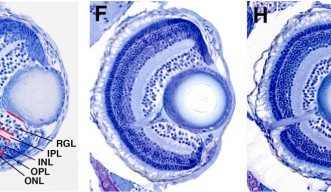

A mutated eye offers a glimpse of a key protein for preventing cancer

Researchers have showcased the central role of a specific protein for stopping cell death and regulating the cell cycle.